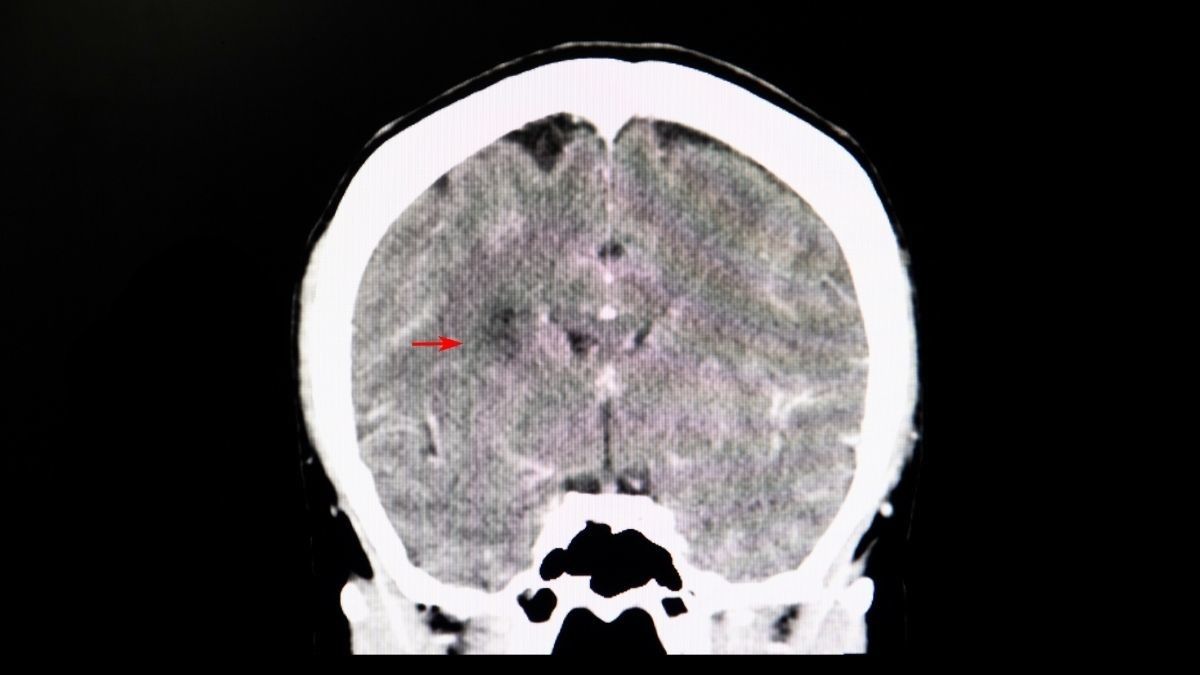

Studi Ungkap Risiko Memori dan Kecerdasan Menurun Akibat COVID-19

Studi yang diterbitkan oleh The Lancet menemukan adanya gejala long covid yang paling umum 6 bulan setelah infeksi. Keluhannya termasuk kelelahan dan masalah kognitif, tak terkecuali brain fog atau kabut otak.

Menurut dr. Devia Irine Putri, memang sudah banyak peneliti yang mengatakan COVID-19 dapat memengaruhi cara kerja otak pasien setelah sembuh. Salah satu yang banyak dilaporkan yaitu brain fog.

“Salah satu gejala long covid yaitu munculnya brain fog atau perkabutan otak, yang bisa menyebabkan keluhan pada pasien COVID-19 seperti sulit berkonsentrasi dan menurunnya daya ingat,” ucap dr. Devia.